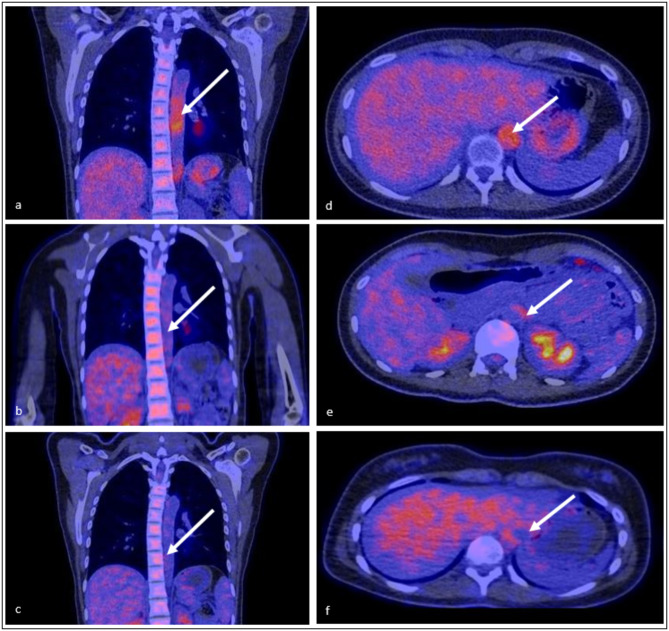

Abstract Image